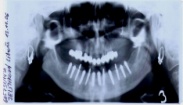

• Dokonalé vyšetření, stanovení diagnózy,naplánování ošetření - způsob, časový průběh,cena

Základní podmínkou pro ošetření pomocí implantátů je dostatečné množství zdravé, kvalitní kosti v čelistech. Dalším důležitým předpokladem je dokonalá ústní hygiena. Také celkový zdravotní stav pacienta hraje významnou roli. Některá systémová onemocnění, jako je diabetes, hypertenze, onemocnění žláz s vnitřní sekrecí, užívání některých skupin léků apod. mohou v některých případech ovlivnit úspěšnost implantace. Také nadměrné kouření či užívání alkoholu nebo jiných návykových látek mohou způsobit komplikace při ošetření pomocí implantátů. Vždy je nutné o těchto záležitostech informovat svého zubního lékaře!

Průměrná doba hojení implantátů před provedením definitivního protetického ošetření je 3-4 měsíce, v případech, kde je nutné doplnit chybějící kost (různé metody, postupy a materiály) – tzv. augmentace) se může doba hojení prodloužit na 8-12 měsíců. S tím je pacient vždy předem seznámen svým lékařem.